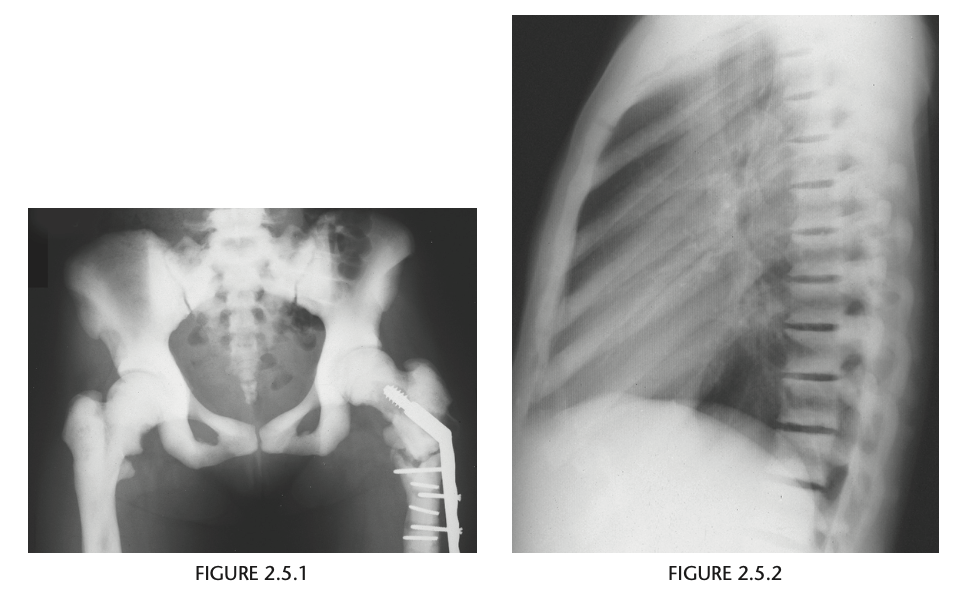

An anteroposterior view of the pelvis

shows flaring of the metaphyseal regions of

the proximal femurs and numerous osteochondromas

arising from the right iliac crest, pubic bones, and proximal right femur (arrows).

Axial CT through upper pelvis - Large right exostosis with soft tissue mass.

AP radiograph of knee - multiple osteochondromas arising from femur and fibula.

DIAGNOSIS: Multiple hereditary exostosis

AD disorder age 10-20s

Signs of malignant transformation - Growth of previous stable exostosis, new or increasing calcifications, new bony erosion

Associated with chondrosarcoma